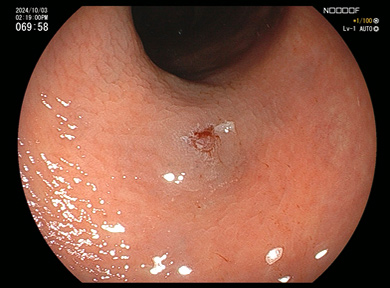

ポリープ切除術

4

ポリープを切除、血液のにじみはわずかです。